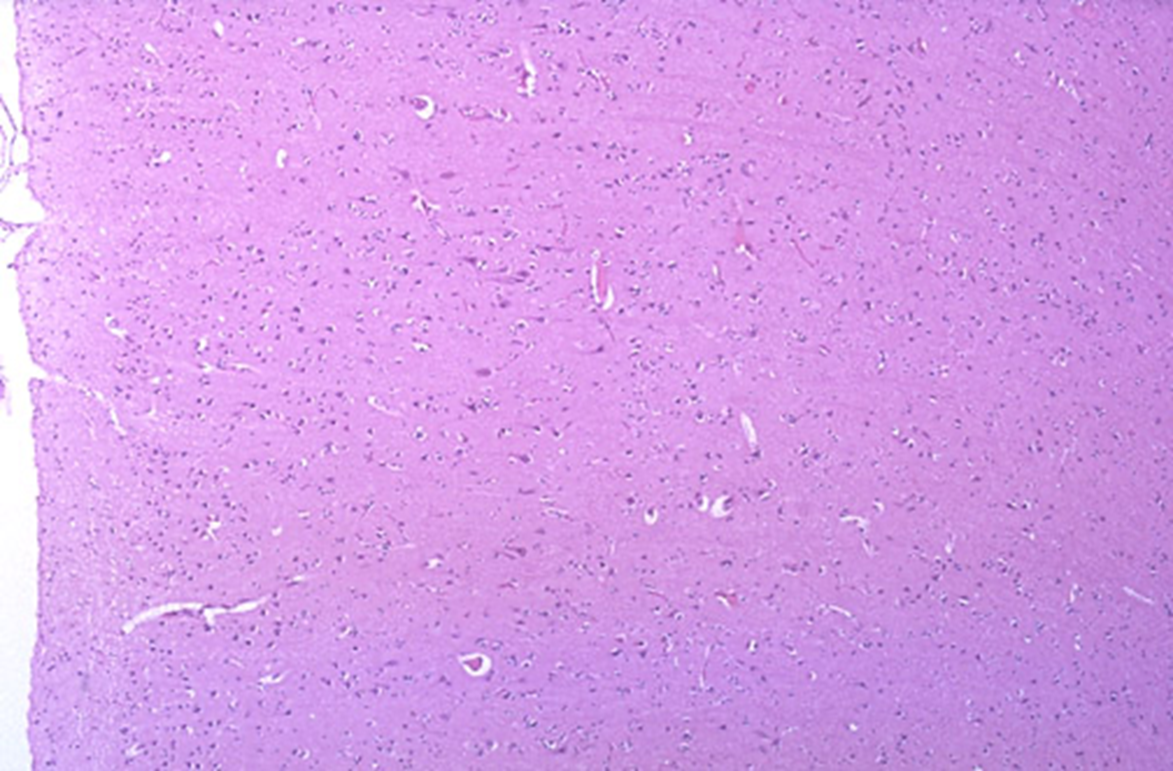

Diffuse Astrocytoma, WHO Grade II

Infiltrating pleomorphic glial cells with increased cellularity

light in color edematous astrocytes

Neoplastic vs normal white matter

Astrocytoma WHO grade 2